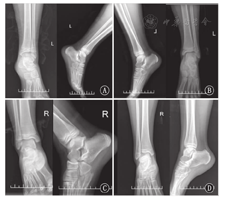

39例患者随访5~91个月,平均35个月。AOFAS评分系统评判结果为优27例,良10例,一般2例。患者踝关节稳定,抽屉及内外翻试验均阴性,无步态异常。患儿均能参加正常的体育活动。9例患者偶有运动后踝关节轻度疼痛。随访中患者均行X线复查。空心钉拔除后1年患儿均接受踝关节X线复查,无骨骺早闭病例(图3)。检查结果显示所有病例均骨性愈合,未发现关节面不平整现象,未发现双下肢不等长和踝关节畸形。39例患者伤口愈合良好,无伤口感染发生。全部病例中已有28例内固定物取出,其中1例术前发现空心钉折断,选用专用空心钻完整取出,未伤及骺板和关节面(图4)。

A:Salter-Harris Ⅱ型骨折;B:Salter-Harris Ⅲ型骨折;C:Triplane骨折;D:Tillaux骨折

A:Ⅱ type Salter-Harris fracture;B:Ⅲ type Salter-Harris fracture;C:Triplane fracture;D:Tillaux fracture